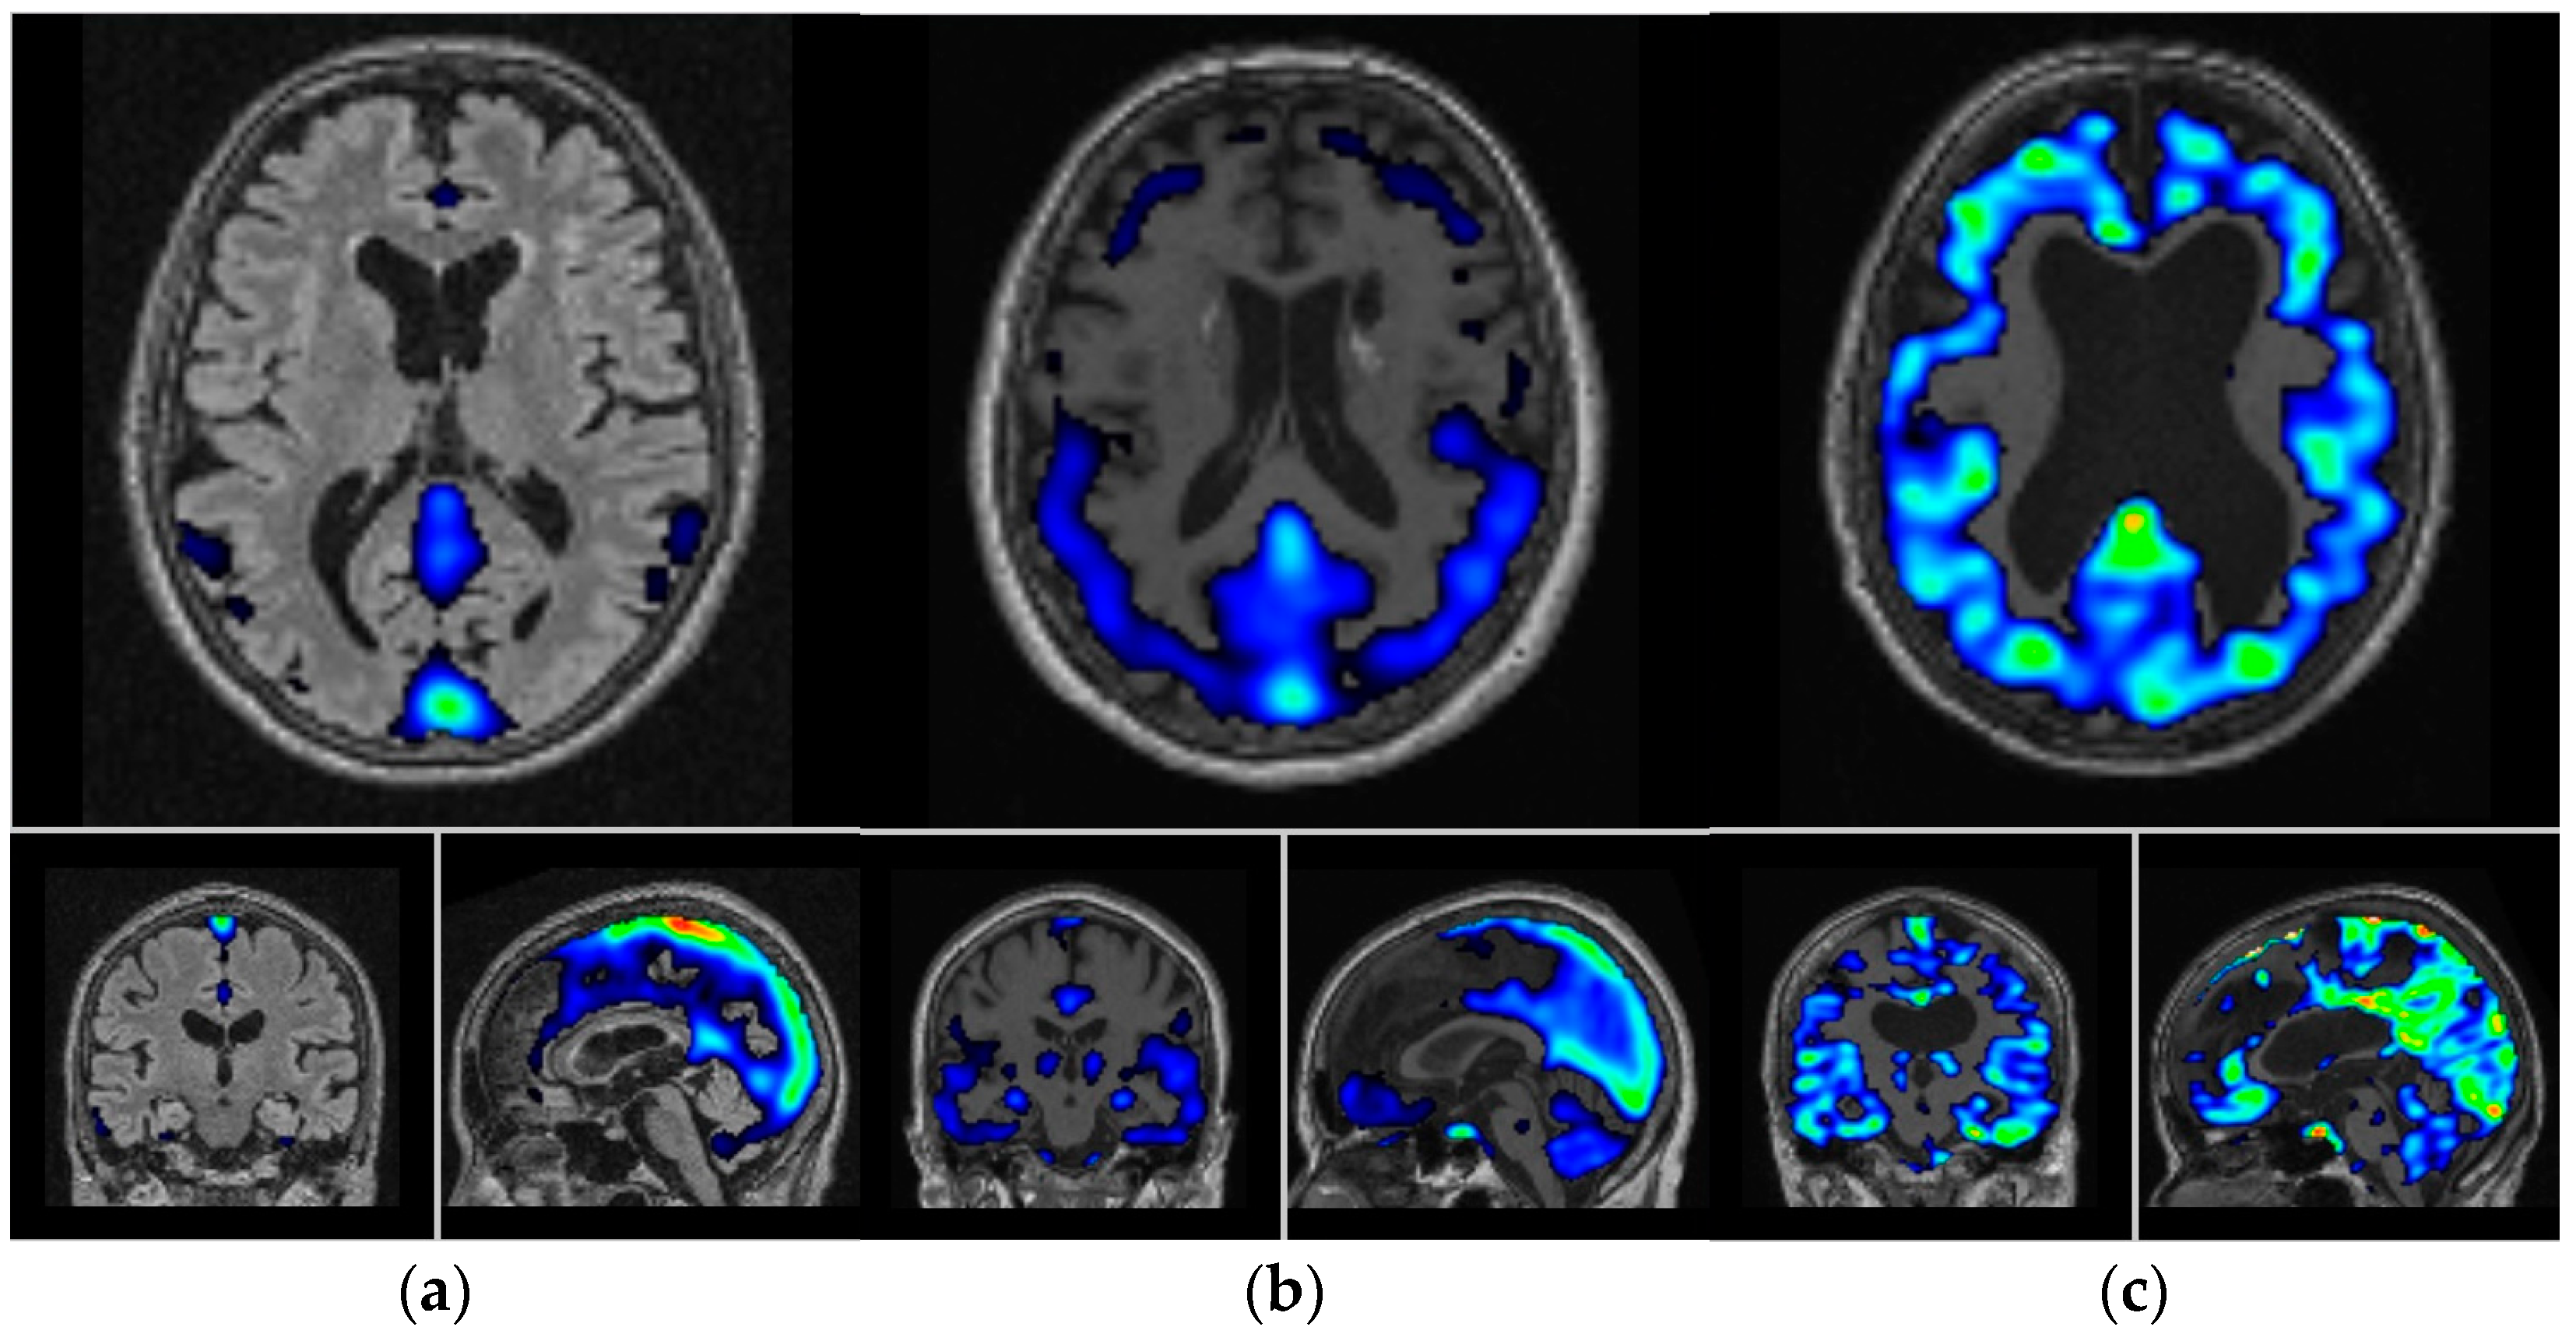

- Yousefzadeh-Nowshahr, E.; Winter, G.; Bohn, P.; Kneer, K.; von Arnim, C.A.F.; Otto, M.; Solbach, C.; Anderl-Straub, S.; Polivka, D.; Fissler, P.; et al. Quantitative analysis of regional distribution of tau pathology with 11C-PBB3-PET in a clinical setting. PLoS ONE 2022, 17, e0266906. [Google Scholar] [CrossRef]

- Yousefzadeh-Nowshahr, E.; Winter, G.; Bohn, P.; Kneer, K.; von Arnim, C.A.F.; Otto, M.; Solbach, C.; Anderl-Straub, S.; Polivka, D.; Fissler, P.; et al. Comparison of MRI-based and PET-based image pre-processing for quantification of 11C-PBB3 uptake in human brain. Z. Fur Med. Phys. 2021, 31, 37–47. [Google Scholar] [CrossRef] [PubMed]